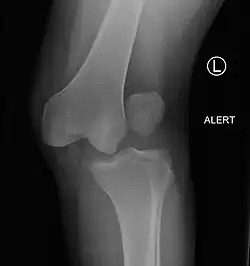

![]() | |

| Plain lateral X-ray of the left knee showing a posterior knee dislocation[1] | |